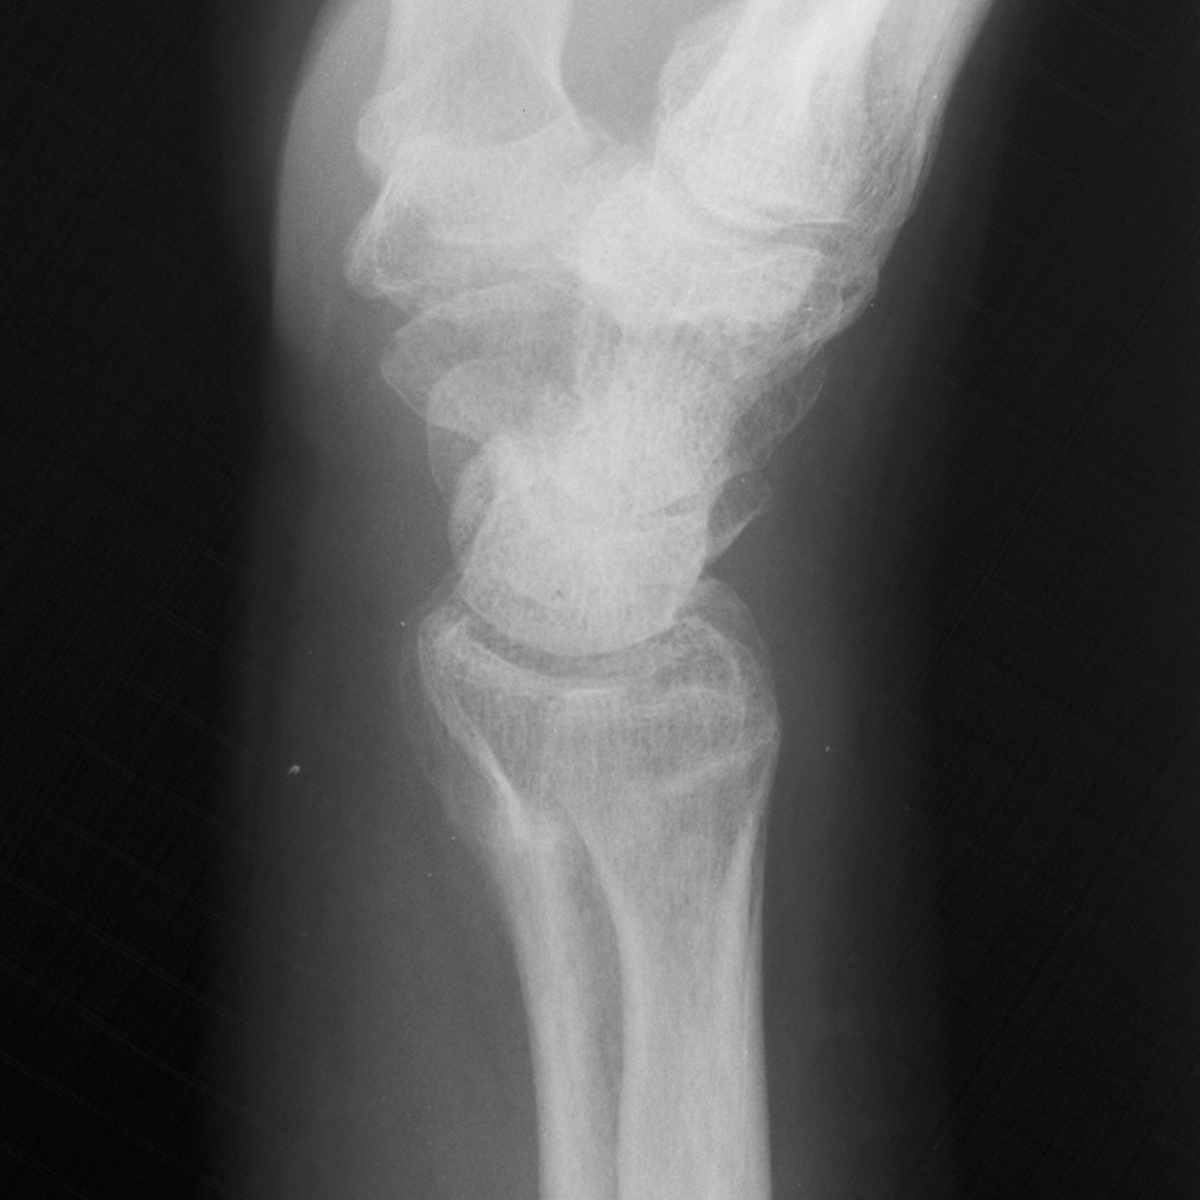

| Case 6 Extraarticular distal radius fracture with angulation and dorsal comminution. |

| Attempts at

closed reduction alone were unsuccessful. |

| Freer elevator

introduced percutaneously as a reduction aid. |

| Percutaneous

fracture stabilization with three pins via the

dorsal radial tubercle, radial styloid and FCR

portals. |

| Pins were left

protruding and bent to overlap. |

| Thermoplastic-pin

construct at 6 weeks, immediately prior to removal. |

| Late result. |